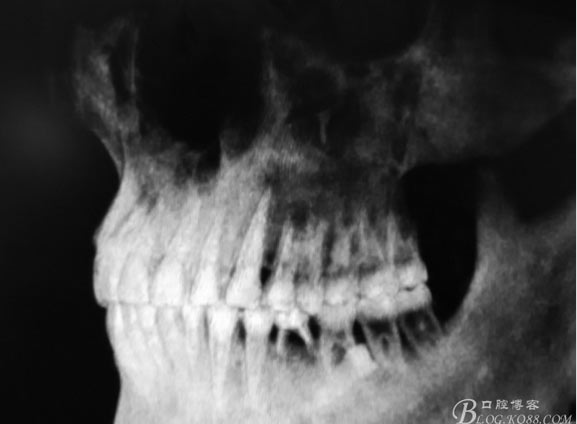

患者、盧xx、男、19歲。主訴:左側下頜乳磨牙未脫落,要求檢查。??茩z查:左側下頜第二乳磨牙有充填物。無松動,全景片檢查。35移位至36、37之間。頰舌側均不能觸及隆起。CBCT檢查:35位于36、37的舌側。表面骨質約2mm左右。35完全骨埋伏,36的遠中牙根疑是吸收。建議35暫觀察。置留不取。患者要求拔除擔心壓迫36牙根或者發(fā)生囊性變。術前簽手術同意書。

圖1.術前的全景片影像檢查,35移位至36、37之間。